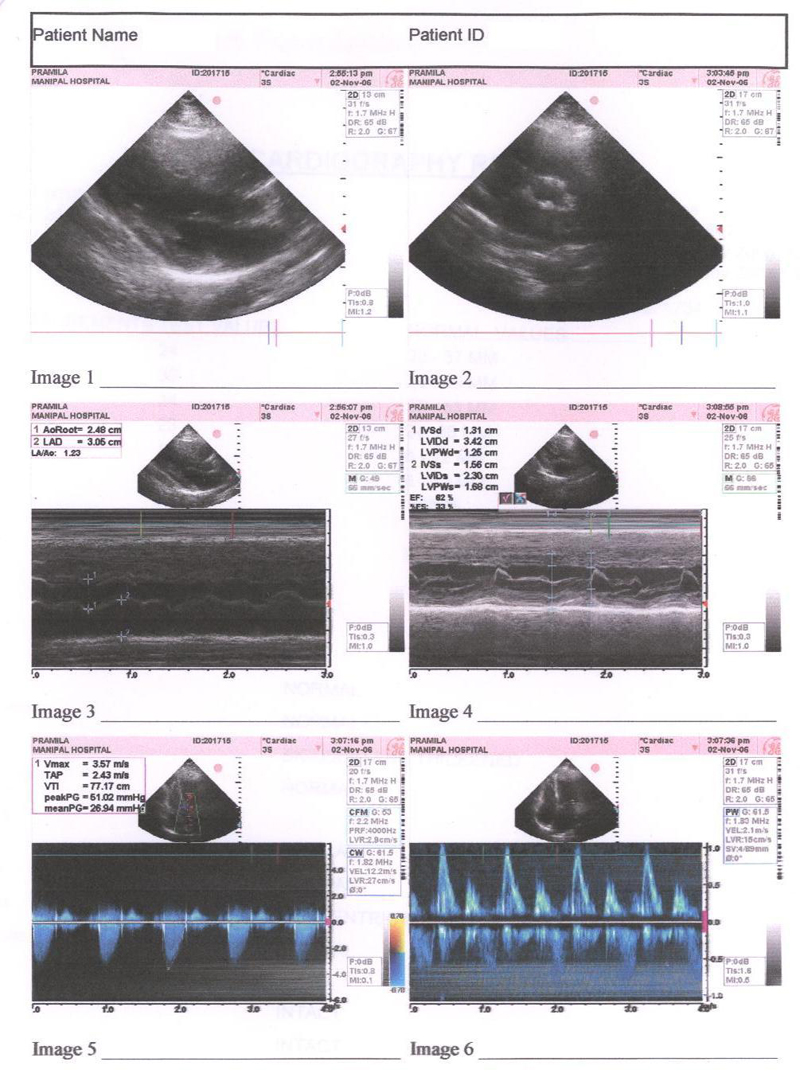

Echocardiography was done and shows that the valves are much better, the abnormal murmur heard using stethoscope have almost disappeared. Echocardiography report is shown in FIG3. Placebo continued

FIG 3:- Echocardiography report of 27th Nov. 2007